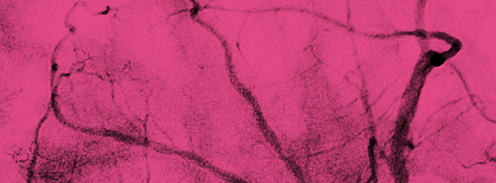

Webinar: Let's discuss strategy! - Folge 20 "ACS bei Spiraldissektion"

Welche Strategie hätten Sie gewählt? In der Webinarreihe "Let's discuss strategy!" von den Leitenden der Rubrik Vaskuläre Herzerkrankungen, PD Dr. Luise Gaede und Prof. Tommaso Gori, wird in der 20. Folge der Fall: "ACS bei Spiraldissektion" diskutiert – mitgebracht und präsentiert von Herzmedizin.de-Studiogast PD Dr. Won-Keun Kim.